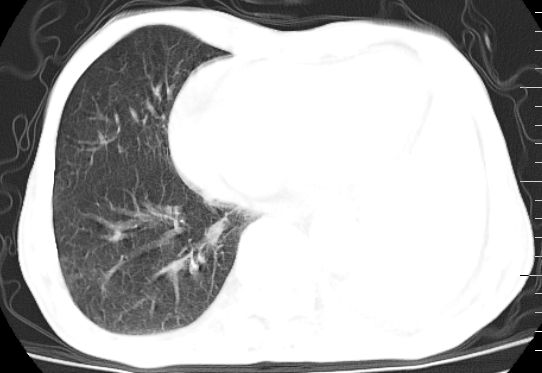

标题: CT10141:男、84岁,咳嗽、咯血1年。 [打印本页]

标题: CT10141:男、84岁,咳嗽、咯血1年。

支持左侧中央型肺癌伴下叶肺不张\\纵隔淋巴结转移.左侧包裹性胸腔积液\\心包积液.左侧少量胸腔积液..慢性支气管炎伴部分间质纤维化.

咯血病史较长,左肺下叶实变,体积未明显缩小,隐约可见血管影及坏死阴影,双肺门及纵隔淋巴结增大,心包增厚积液,纵隔右移位,单侧胸腔积液,首先考虑:大叶型肺泡癌伴纵隔心包转移。